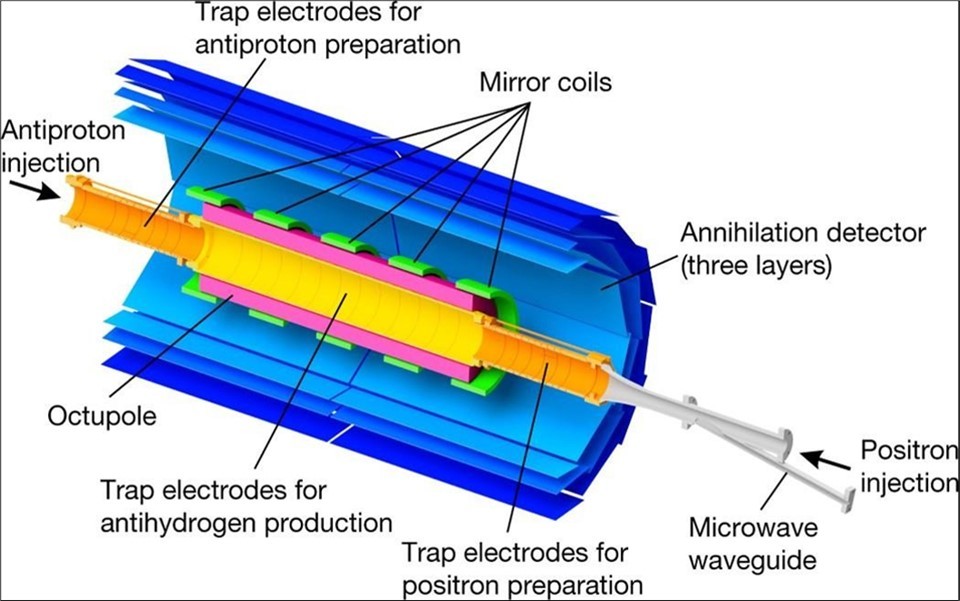

Figure 5.Schematic of different steps of CERN Large Hadron Collider (LHC) radiation source for magnetic resonance biospectroscopy in metabolic and molecular imaging and diagnosis of cancer.